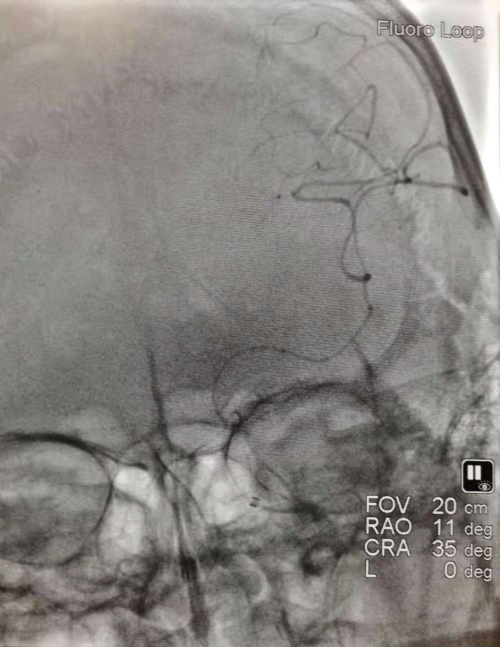

弓上及颅内血管造影

左侧颈内动脉导引导管造影

微导管造影

支架释放、EF远端通路导管到达颈内动脉末端,边抽吸边回收支架